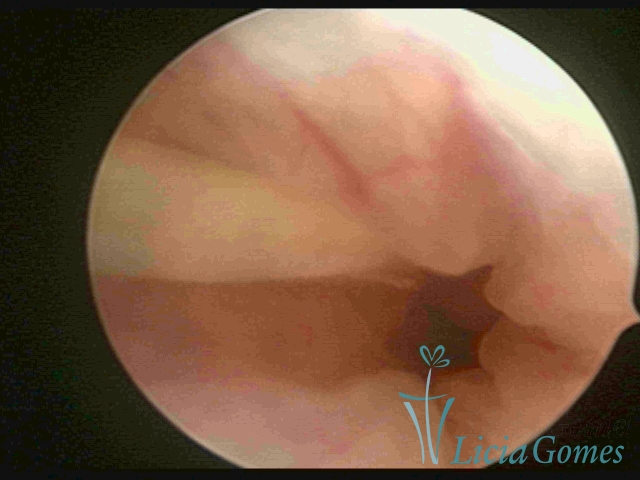

Cervical canal with IUD string